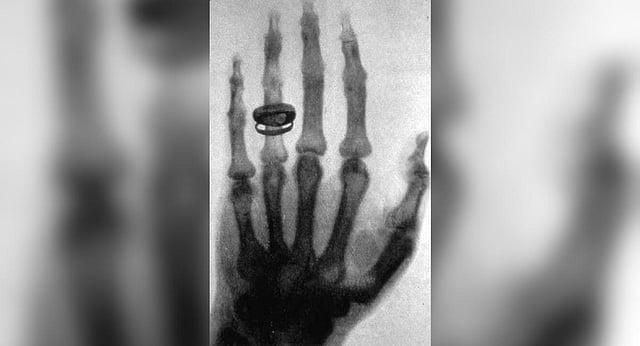

X-ray is a form of electromagnetic radiation with wavelengths shorter than those of ultraviolet light. X-rays were discovered accidentally in the year 1895, by Professor Wilhelm Conrad Roentgen, a German scientist, while he was working with a cathode-ray tube in his laboratory.

He called his discovery, X-rays to indicate that it was, then, an unknown type of radiation. Roentgen was awarded the first Nobel Prize in Physics in 1901. X-rays are also known as Roentgen rays.

One of Roentgen’s first experiments late in 1895 was a film of the hand of his wife, Anna Bertha, which showed bones of her hand and their wedding ring. Interestingly, the first use of X-rays was for industrial applications, as Roentgen produced a radiograph of a set of weights in a box to show his colleagues.